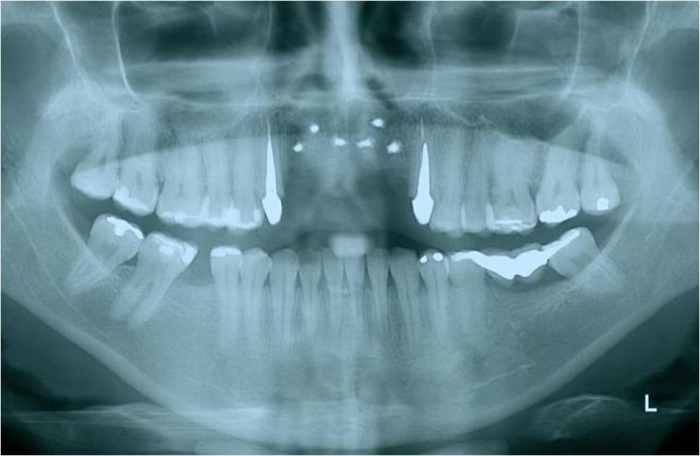

Raio x final